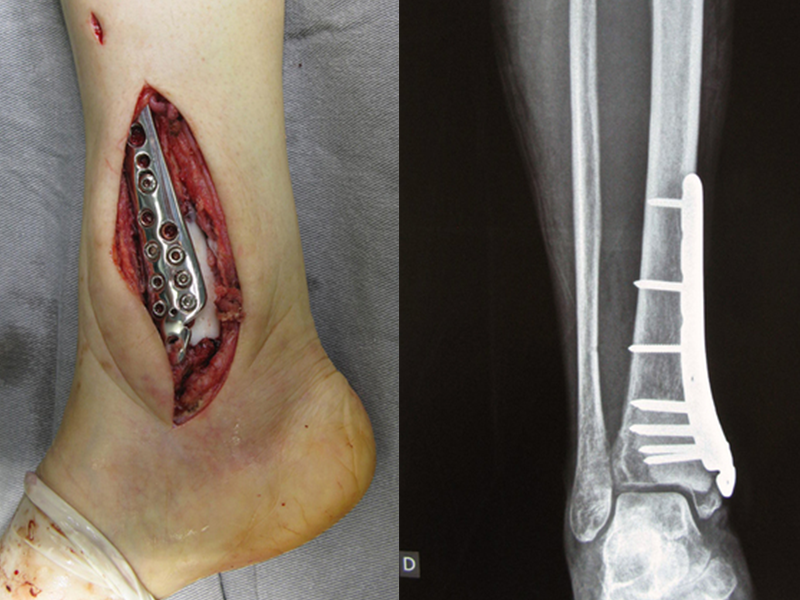

Precisamos ressaltar que a biópsia deve ser executada/acompanhada pelo cirurgião que vai realizar a cirurgia. Sua presença é essencial para que esta seja realizada de acordo com o planejamento da cirurgia.

Não se deve realizar incisões transversas, nem incisões extensas onde não há musculatura para posterior cobertura, como na perna por exemplo. A sutura não deve ter pontos distantes da incisão, pois isto exigirá uma ressecção mais larga de tecido e muito menos realizar-se mais de uma incisão, figuras 79 (quadros A, B, C e D) e 80.

A seguir, exemplificamos dois casos de biópsias realizadas corretamente, figuras 83 a 86.

Vemos, com muita frequência, pacientes com cicatrizes de biópsia realizadas na região ântero-lateral da metáfise distal do fêmur. A seta vermelha aponta a fáscia lata, que na maioria das vezes é interrompida pelo trajeto da biópsia, realizada por profissionais que não vão operar o paciente, dificultado a cobertura da futura cirurgia e a função deste membro que precisará ser reconstruído.

A seta amarela indica o trajeto póstero-lateral, mais adequado para a biópsia e para a reconstrução, propiciando a melhor cobertura e função.

Para a realização da biópsia por este trajeto o posicionamento adequado do paciente é em decúbito prono, figuras 119 a 122.

O tratamento de tumores da extremidade distal do fêmur, como esta lesão, com este grau de comprometimento e localização, indicamos a biópsia conforme descrevemos e a realização de quimioterapia neoadjuvante de indução, ressecção com margem oncológica e reconstrução com prótese modular e quimioterapia adjuvante.